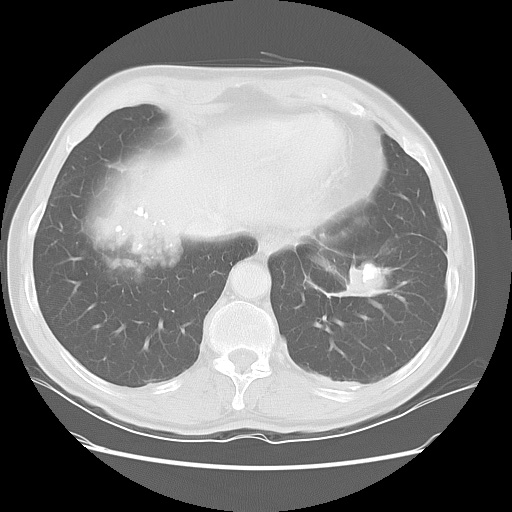

Scott WilliamsPETPET > PET tumor imaging > Neuroendocrine tumorsJanuary 26, 2015PETPET > PET tumor imaging > Other neoplasmsFebruary 23, 2014Cardiac ImagingCardiovascular > Perfusion Exam FindingsFebruary 20, 2014Cardiac ImagingCardiovascular > Perfusion Exam FindingsFebruary 20, 2014LymphoproliferativeLymph > Nodular lymphoid hyperplasiaFebruary 12, 2014Infections-InflammatoryInfect > Fungus > FusariosisFebruary 12, 2014CongenitalCongenital > ImmunoFebruary 9, 2014CardiacCardiac > Congenital > Noncompaction cardiomyopathyFebruary 5, 2014HomeAsbestos > Images > Round atelectasis case 1August 13, 2012HomeAsbestos > ImagesAugust 13, 2012Previous PagePage 4 of 265Next PageTop StoriesDigital X-RayChest x-rays reveal atherosclerosis in patients undergoing amputationsLower limb amputation is an increasingly common major complication of advanced peripheral arterial disease and diabetes mellitus.MRI3D MRI technique helps plan treatment for pediatric heart conditionsWomens ImagingCould AI scoring help with managing DCIS?CTClinicians, beware: CT diagnostic accuracy varies by adnexal lesion typePractice ManagementRadiology coding update for 2026